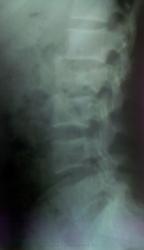

Пол пациента: Мужской пол Тип патологии: Травма Область исследования: Скелетно-мышечная система Методы исследования: Rg Молодой мужчина. В силу неизвестных (врачам естественно, сам то он знает) обстоятельств "вышел" в окно третьего этажа. Сложности случай не представляет. "Чисто" посмотреть. Переводится в нейрохирургию. https://radiomed.ru/sites/default/files/styles/case_slider_image/public/user/2667/foto002_0.jpg?itok=JBtmPNiW ID:9653 Чт, 02/12/2010 - 02:43 #1 Helios Не на сайте Был на сайте: 7 месяцев 3 недели назад Зарегистрирован: 06.08.2010 - 15:16 Публикации: 4417 Третий еще ничего.Наш сосед с 4-ого пролетел, 3 позвонка сломал, пятки-через 3 месяца бегал не хуже, чем в молодости.